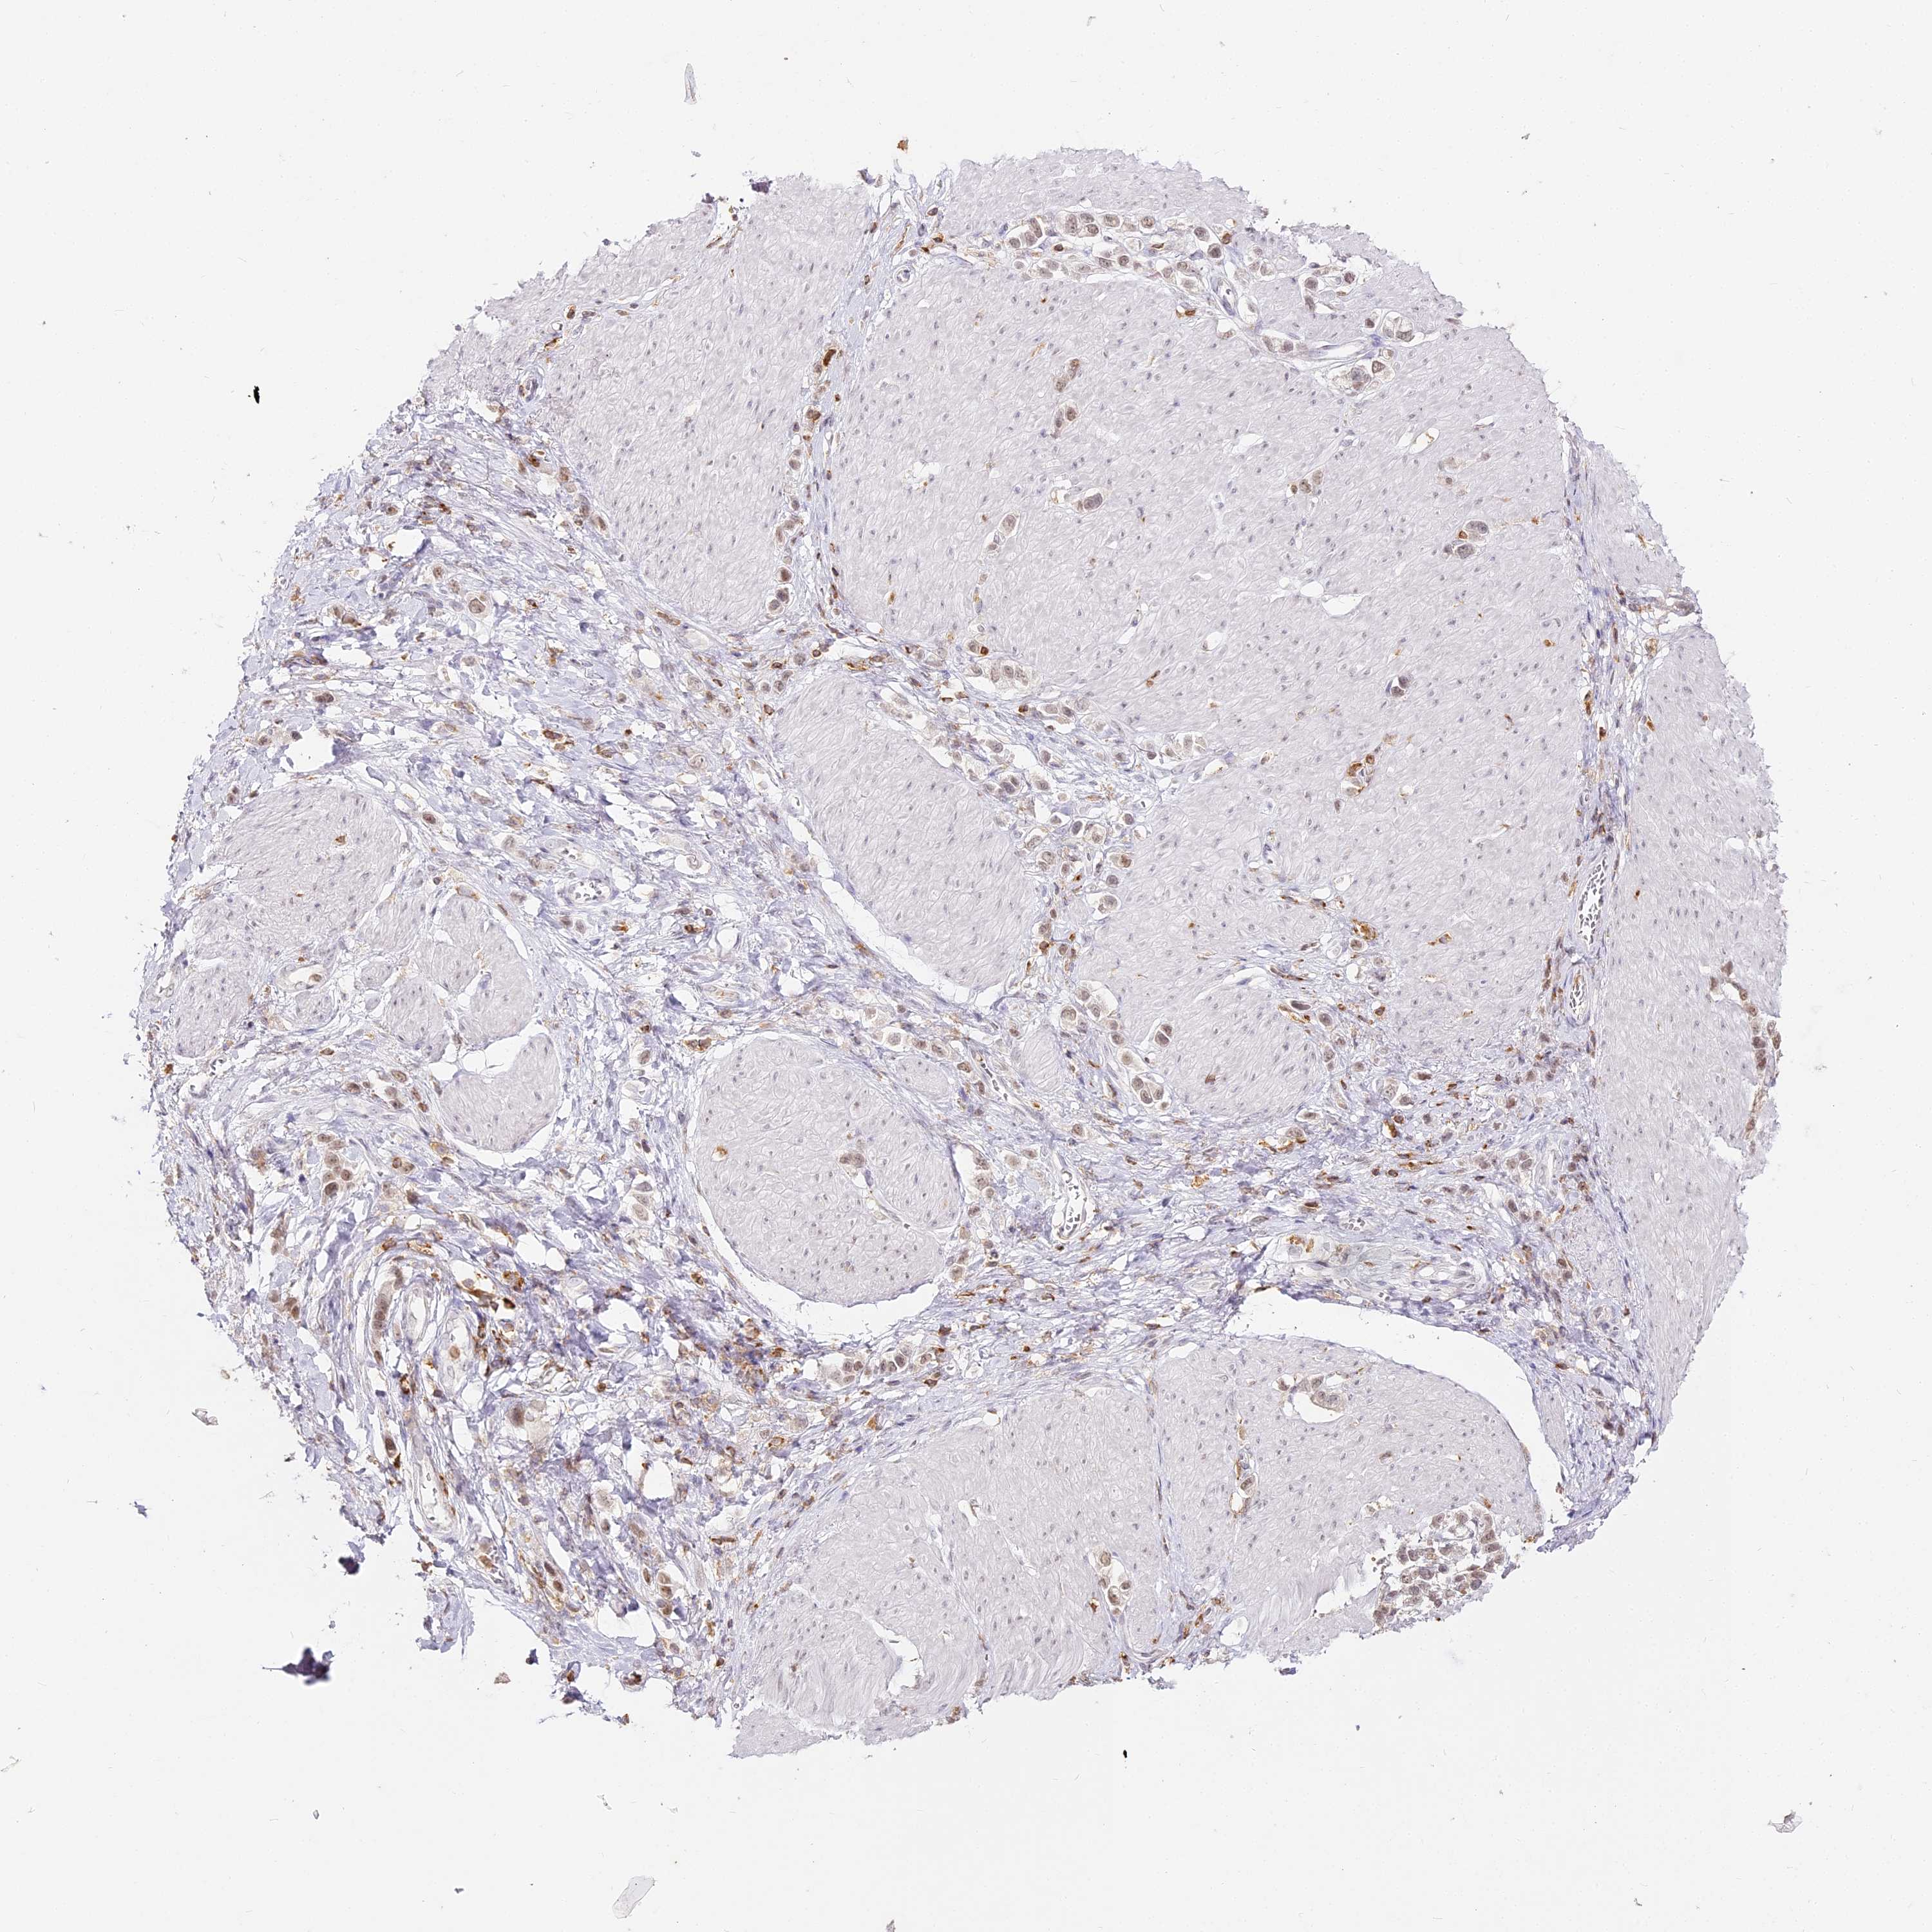

STOMACH CANCER - Protein expressioni

A mouse-over function shows sample information and annotation data. Click on an image to view it in a full screen mode. Samples can be filtered based on level of antibody staining by selecting one or several of the following categories: high, medium, low and not detected. The assay and annotation is described here.

Note that samples used for immunohistochemistry by the Human Protein Atlas do not correspond to samples in the TCGA dataset.

Antibody stainingi

Antibody staining in the annotated cell types in the current human tissue is reported as not detected, low, medium, or high, based on conventional immunohistochemistry profiling in selected tissues. This score is based on the combination of the staining intensity and fraction of stained cells.

Each image is clickable and will lead to virtual microscopy that enables deeper exploration of all samples and also displays staining intensity scores, fraction scores and subcellular localization as well as patient and tissue information for each sample.

Antibody HPA036469

Staining

High

Medium

Low

Not detected

Intensity

Strong

Moderate

Weak

Negative

Quantity

>75%

75%-25%

<25%

None

Location

Nuclear

Cytoplasmic/membranous

Cytoplasmic/membranous,nuclear

Adenocarcinoma, NOS